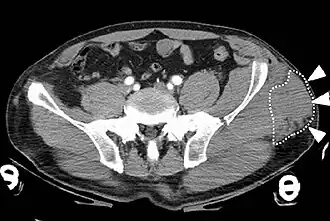

Le syndrome de Morel-Lavallée (SML) ou lésion de Morel-Lavallée (MLL) est un type de blessure[1] caractérisée par un épanchement de liquide sérolymphatique consécutif à un traumatisme qui survient de manière tangentielle[3] sur un tissu fortement vascularisé. Ce traumatisme provoque la désolidarisation des tissus cutanés et sous-cutanés par rapport aux couches musculaires et aux fascias situés en-dessous, sans rupture de la peau[4],[5]. À la suite de ce décollement cutané, se crée un espace dans lequel le liquide sérolymphatique s'accumule.

La lésion se situe généralement au niveau de la cuisse ou du bassin ; même si d'autres régions du corps peuvent être impliquées[1]. Les symptômes comprennent des ecchymoses, une mobilité cutanée accrue et un gonflement[1]. Cela peut ne pas apparaître avant quelques jours[1]. Les complications peuvent consister en une infection ou une anomalie de la zone concernée[1].

Les blessures associées peuvent inclure des fractures du bassin ou du fémur[1]. Le mécanisme sous-jacent implique la séparation du tissu sous-cutané du fascia situé en dessous, sans rupture de la peau[1], Cela crée un espace dans lequel le fluide s'accumule[2]. Le diagnostic se fait à partir d'un examen physique et peut être étayé par imagerie médicale[1].

Le diagnostic est basé sur l'examen clinique et peut être étayé par l'imagerie médicale[7].